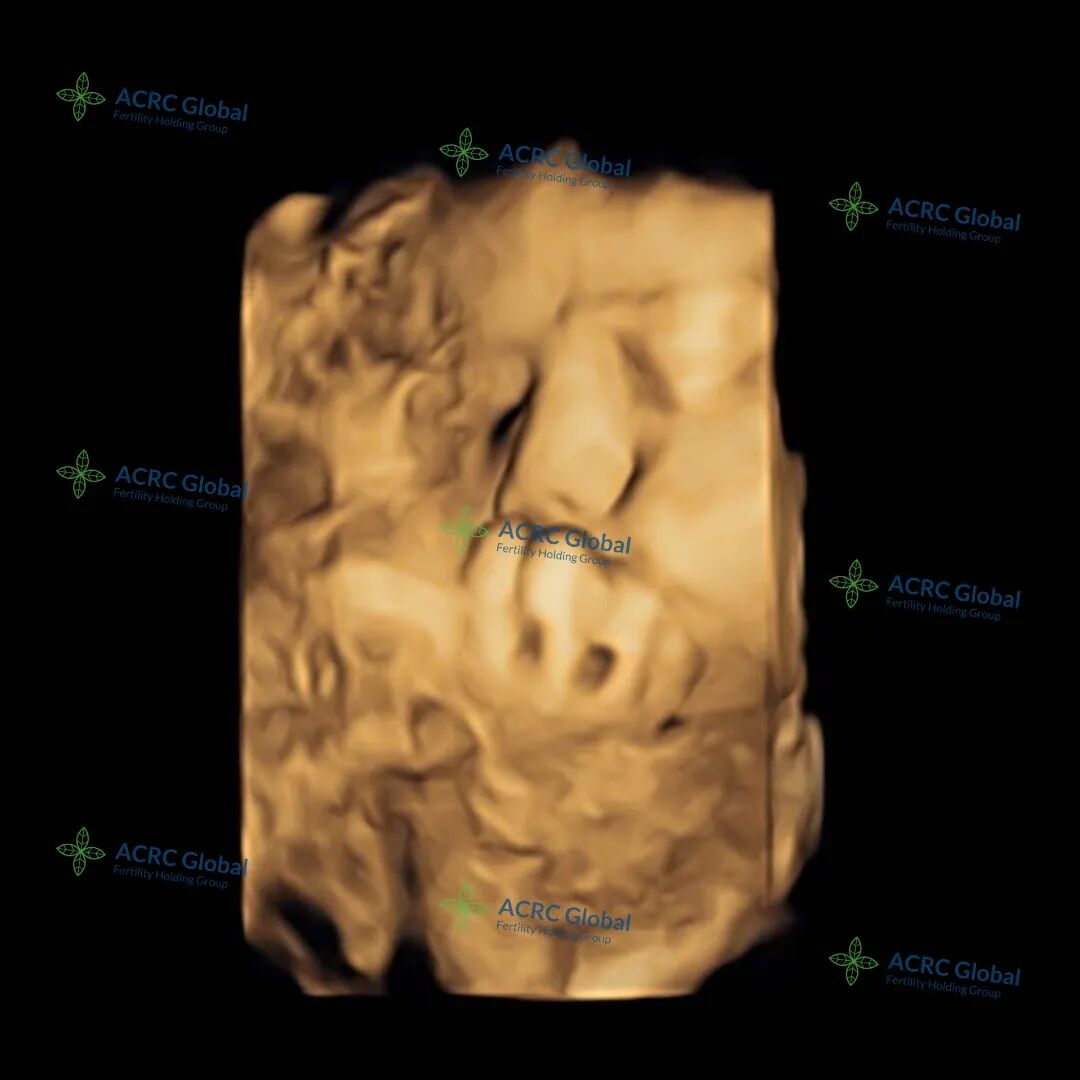

爱妈E的三维B超显示,宝宝已经37周了,体重达到六磅多,已经足月,小脸蛋看上去圆润饱满、十分可爱。虽然小手轻轻挡住了脸蛋,但从侧脸的轮廓中依然可以看出她那精致的小公主模样。医生预估,宝宝在出生时将会有七磅左右。准父母已经满怀期待地准备迎接宝宝的到来,期盼着和她的第一次见面呢!